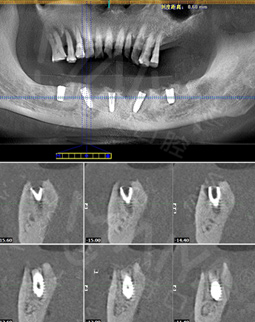

麦芽的博士专家团在看过我的片子后发现,我的牙齿由于长期对口腔疏于护理,牙周情况非常差,余牙有些松动,且牙槽骨萎缩严重,现存的骨量无法进行传统的种植牙手术,因此给我设计了“all-on-4”种牙技术的升级版本“all-on-5”,前期是要处理我的牙周问题,当天就给安排了洁牙,然后上药,等牙周恢复差不多就可以进行种植了!

经过一个月的牙周治疗,牙齿肿胀部分都已经消退,来麦芽种牙之前,心理还有点小紧张,总害怕种牙特别疼,恢复时间慢。我的牙齿情况比较复杂,部分牙齿有牙槽骨吸收,经过前期的各种检查,医生说我的身体状况适合种牙。

但是打完麻药,躺在那里发现手术时一点感觉也没有,半口牙只种了5颗牙钉,而且不到一个小时,感觉自己就眯了一会就好了。麦芽的种植专家们手法特别棒,很稳。牙钉种好之后,没有立即戴牙冠,医生用硅橡胶取模,为我制作了临时牙冠,不过看到临时牙冠我就能想象到完全种好牙的样子了!然后,医生给我一个小卡片,上面记录了种牙后的注意事项,告诉我种完牙后自己维护也很重要。医生说要按时复诊,也会有专门的工作人员进行通知,不得不说麦芽在细节上真的很暖心。